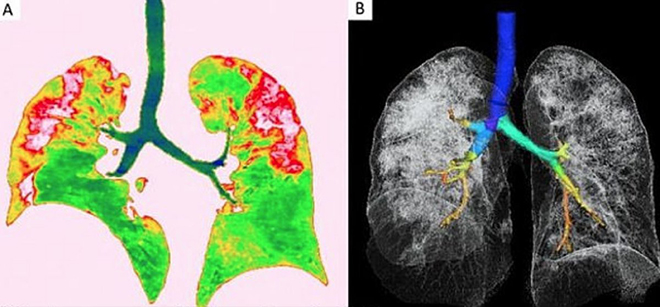

Merkezi ABD’de bulunan Kuzey Amerika Radyoloji Topluluğu tarafından paylaşılan röntgen görüntüleri corona virüsünün ciğerlere nasıl etki ettiğini gözler önüne serdi. Uluslararası basın kuruluşlarına yansıyan görüntülerde Whan’daki deniz ürünleri pazarında çalışan 44 yaşındaki bir corona virüsü hastasının ciğerlerindeki doluluk oranı görülüyor.

Yapılan açıklamada röntgeni çekilen 44 yaşındaki hastanın 25 Aralık 2019’da hastaneye öksürük ve yüksek ateş dolayısıyla gittiği ve tedavi altına alındığı belirtildi. Yetkililer doktorların müdahalesine rağmen hastanın bir hafta sonra öldüğünü aktardı.

İngiliz tabloid gazetesi Daily Mail’deki haberde Wuhan’a gittikten sonra hastalanan 54 yaşındaki bir kadının da ciğer röntgenleri paylaşıldı. Hastanın yüksek ateş, öksürük, halsizlik ve göğüs ağrısı şikayetiyle hastaneye gittiği belirtilirken, hastaya oksijen ve antibiyotik verildiği belirtildi. Japonya’ya döndükten sonra hastanın ilaç tedavisiyle birlikte iyileştiği açıklandı. Haberde, bu tür değişikliklerin SARS ve MERS hastalardakilerine benzediği belirtildi.